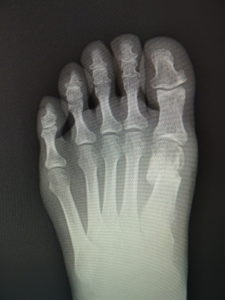

(図5)

手術前 手術後4年

(図6)

手術前 手術後

(図7)